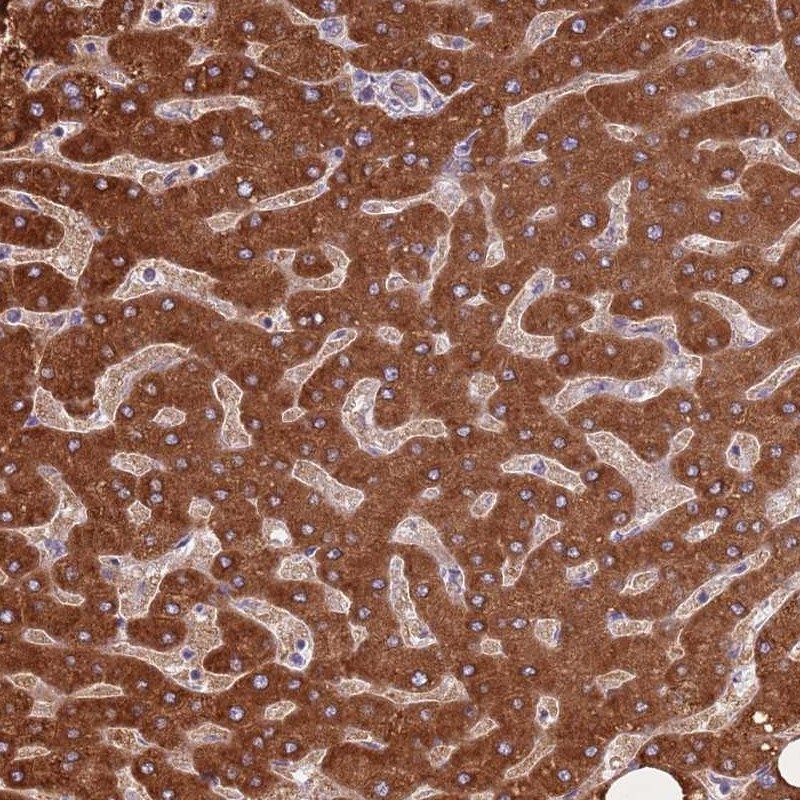

Immunohistochemical staining of human liver shows strong cytoplasmic positivity in hepatocytes.